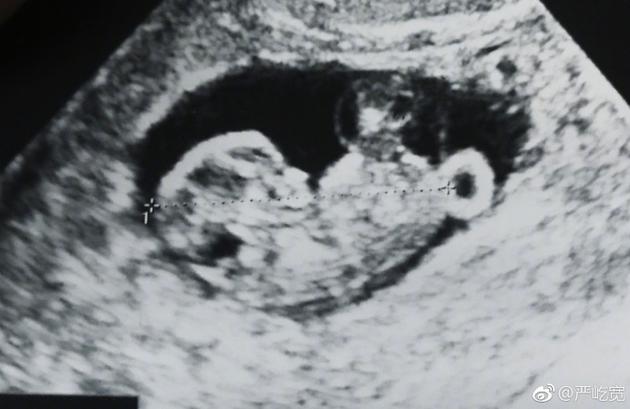

嚴屹寬曬出寶寶的B超照片

新浪娛樂訊 1月24日是嚴屹寬的生日,他在生日當天宣布了即將升級當爸的喜訊,并曬出了妻子杜若溪孕檢的照片,并發(fā)文感謝妻子,稱收到了“最好的生日禮物”。杜若溪隨后轉發(fā)為老公送上生日祝福。

24日早,嚴屹寬在微博曬出妻子孕檢的照片以及兩人的合照宣布妻子懷孕:“收到了最好的生日禮物,感謝我的肉肉”,并艾特妻子杜若溪本人的微博。隨后嚴屹寬將這條微博置頂。在三十九歲生日這天,嚴屹寬宣布妻子懷孕的消息并與網(wǎng)友們分享,一家人幸福滿滿,令人羨慕。